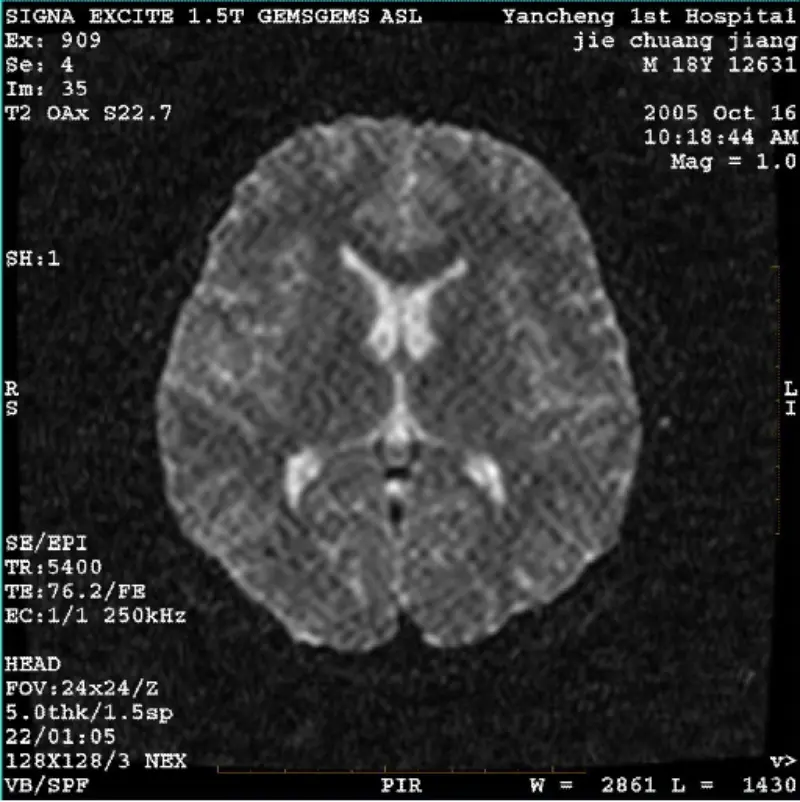

Læs mereSYSTEM: 1.5T Signa Twin Excite II (Softwareversion 11.0M4) PROBLEM/SYMPTO DWI (Zoomtilstand og hel tilstand) og fiesta (zoomtilstand og heltilstand) billede med synligt net- eller fløjlsmønster, uanset når du bruger kropsspole eller hoved spole, virker andet rutinebillede normalt